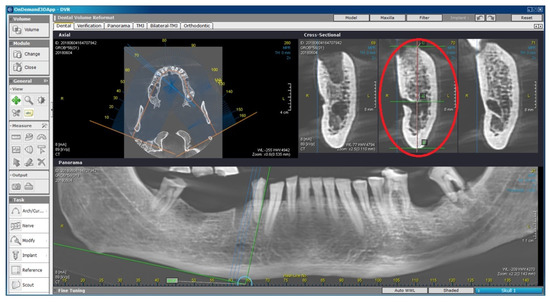

2.2. Radiomorphometric Assessments